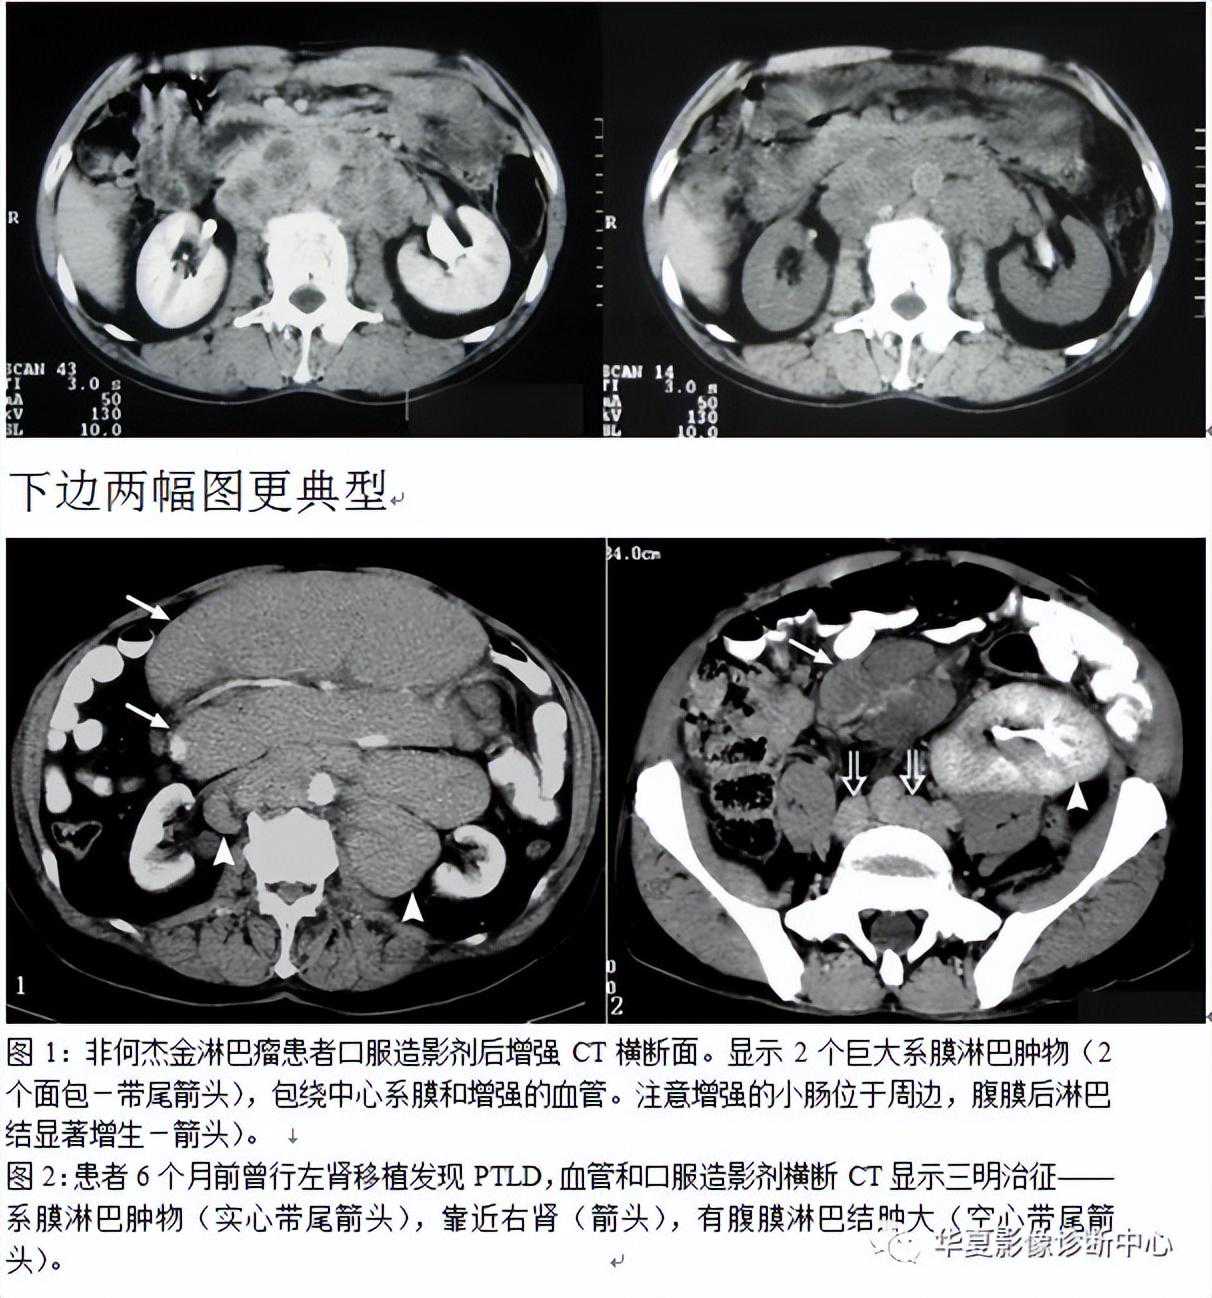

035:三明治征(夹心面包征或夹心饼征)

指2个均质软组织肿物组成三明治面包,系膜脂肪和管状物为构成夹心,是腹部CT横断扫描时的影像表现。系膜脂肪和血管组成夹心,肿大淋巴结组成面包;在给予增强剂后系膜管状结构(血管、肠管)相对脂肪增强,夹心层突出。因为淋巴结增大会压迫血管,阻碍静脉回流,使夹心层内增强的血管更加明显。当经静脉及口服造影剂后,肠系膜血管结构较脂肪明显强化,从而可使夹心更加突出。导致肠系膜淋巴结肿大的病因很多。除淋巴瘤外,癌、肉瘤、类癌、获得性免疫缺陷相关性淋巴结增生综合征、结核、肠源性脂肪代谢碍及炎症性肠病等也是最常的病因。

癌、肉瘤及类痛均可起源于小肠,然后向肠系膜淋巴结扩散。这些肿瘤快速侵犯肠壁而导致穿孔、出血及弥漫性病变。感染性及炎性病变通常不会引起巨大的块状淋巴结肿大,它们所引起的淋巴结肿大,通常表现为中央坏死,周边可见环形强化,此点与结核相似。因此这些肿瘤,感染及炎性病变不会产生三明治征。

三明治征为肠系膜淋巴瘤的特异征象。因为只有在肠系膜淋巴瘤中淋巴结才可以长得很大,并包绕脂肪、肠管和血管而不产生任何临床症状。肠系膜淋巴瘤偶尔可侵犯浆膜及固有肌层,有时会引起小肠出血但极少引起游离性穿孔。肠系膜淋巴瘤还可以引起腹膜后淋巴结肿大。

绝大多数肠系膜淋巴瘤是非霍奇金淋巴瘤。过去在临床上通常难以确定非霍奇金淋巴瘤是否累及肠系膜。随着现代影像技术的发展及影像检查的普及.非霍奇金淋巴瘤累及肠系膜及其所表现的三明治征经常可以见到。

患者的免疫功能紊乱是非霍奇金淋巴瘤的危险因素。例如.AIDS患者易于并发非霍奇金淋巴瘤,这与AIDS相关性淋巴结增生综合征有本质的区别。随着实质器官移植及骨髓移植的增多,移植后淋巴组织增生性疾病有增多趋势。淋巴组织增生性疾病为EB病毒驱动的B细胞增殖性病变,在形态学上淋巴组织增生性疾病与侵袭性非霍奇金淋巴瘤难以区别,但由于发病机制及临床处置均不相同.因此,可将淋巴组织增生性疾病看作一种独立的淋巴增生性疾病。淋巴组织增生性疾病通常累及胃肠道.但不引起浅表结节样的改变。对于行器官移植的患者,如果断层影像显示夹心面包征,必须考虑到存在淋巴组织增生性疾病的可能性。

总之,三明治征指的是CT柏横断面上,巨大增生的肠系膜淋巴结包绕肠系膜脂肪和血管而形成的类似三明治的影像。对于设有移植病史的患者,非霍奇金淋巴瘤是三明治征的主要病因;有移植病史的患者,产生三明治征的原因则可能是淋巴组织增生性疾病,随着接受移植手术的患者不断增多,三明治征可能会在临床上越来越常见。下图是一个恶性肿瘤腹膜后淋巴结转移患者: